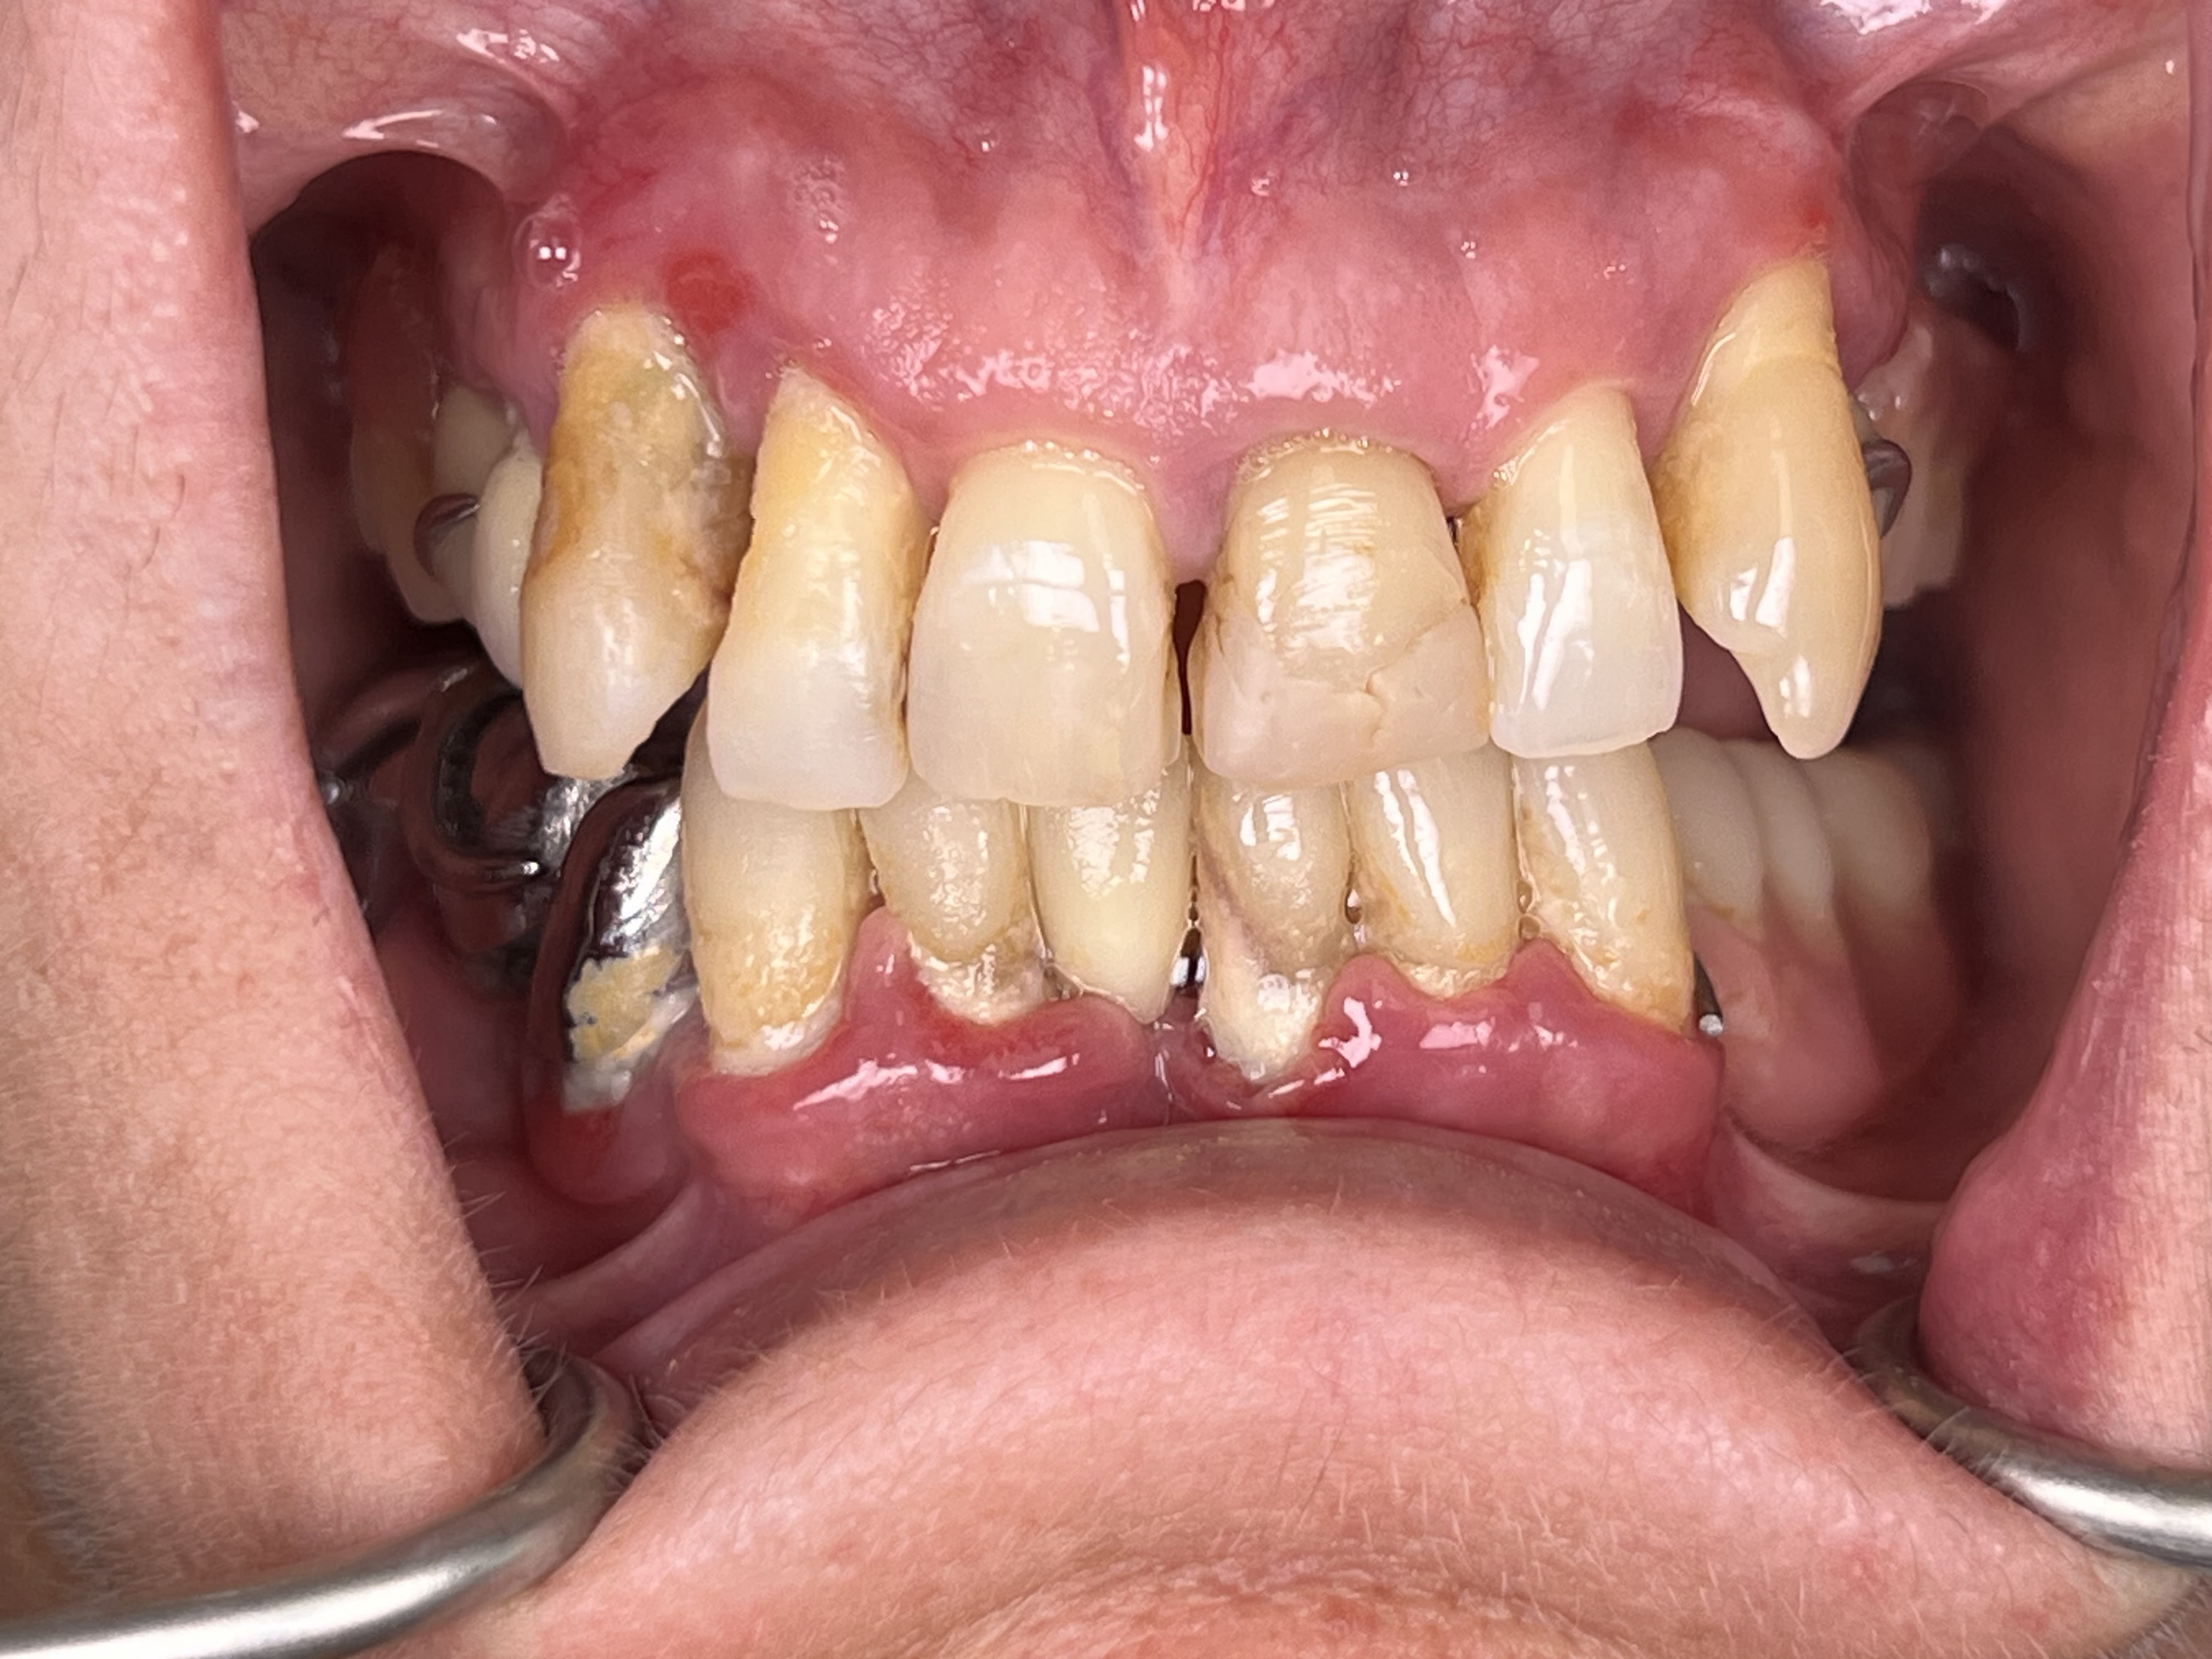

J'ai fais un comparatif (j'ai du compressé à 2mo la taille maxi pour eugénol)

1) iphone 13 pro objectif x1 + macro 75mm + flash led (je suis a 5-10cm du patient)

2) iphone 13 pro objectif x3 + flash led (je suis a 20-40 cm)